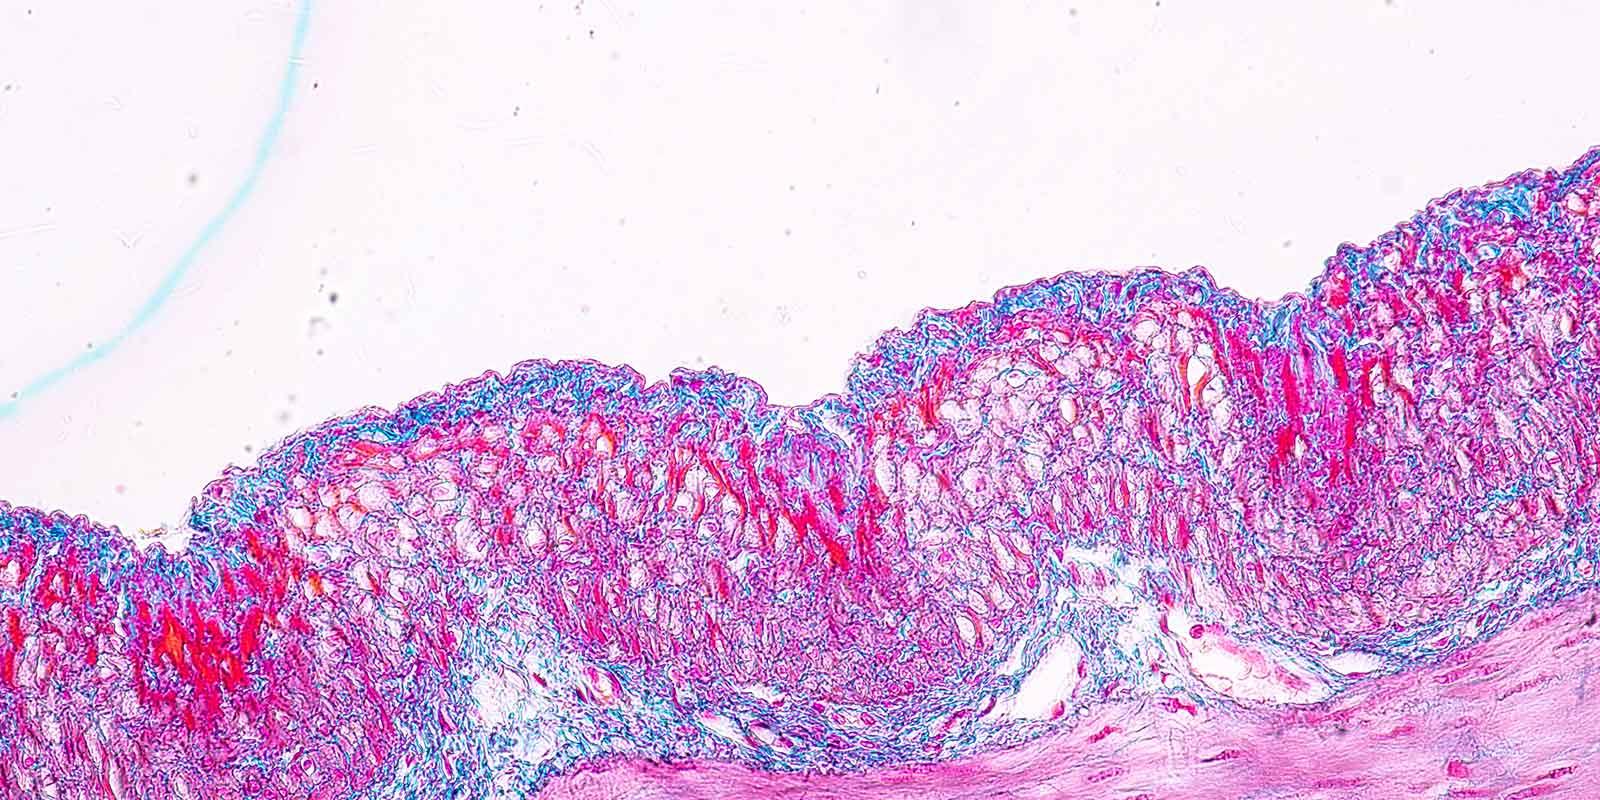

The Digestive Health Institute at University Hospitals is recognized nationally and internationally for its contributions to diagnostic/therapeutic endoscopy, inflammatory bowel disease and GI outcomes research.

The UH Digestive Health Institute provides all patients high-quality care with patient-centered experiences and access to innovative research to improve the health of the communities we serve. The following programs continue to flourish with important research accomplishments and publications: Inflammatory Bowel Disease, Barrett’s Esophagus and Esophageal Cancer, Hepatology, Health Services, and Outcomes Research.

The Digestive Health Institute has an important history in discovery and innovations in the field of gastroenterology.